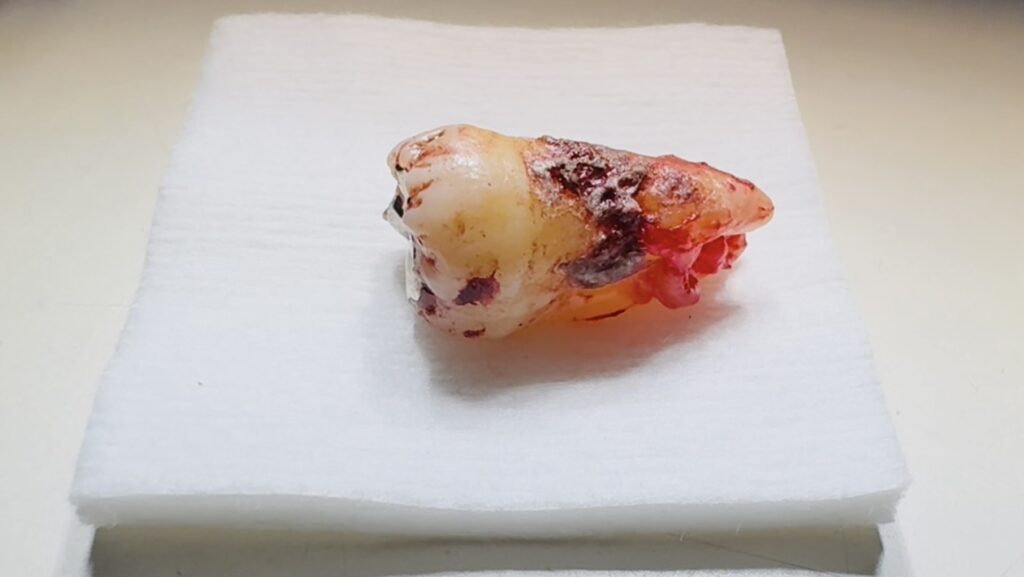

【症例CASE2】 抜歯になった歯 (※実際の症例写真を掲載しています。苦手の方はご注意ください。)

最後の写真は、歯石が長年覆い、抜歯になった歯です。

小さな炎症を長い間、放置した結果、小さな歯石は、歯を支える周囲の骨を吸収するほどに大きくなります。

ここまで進行すると、歯を残したくても残すことができなかった実例です。